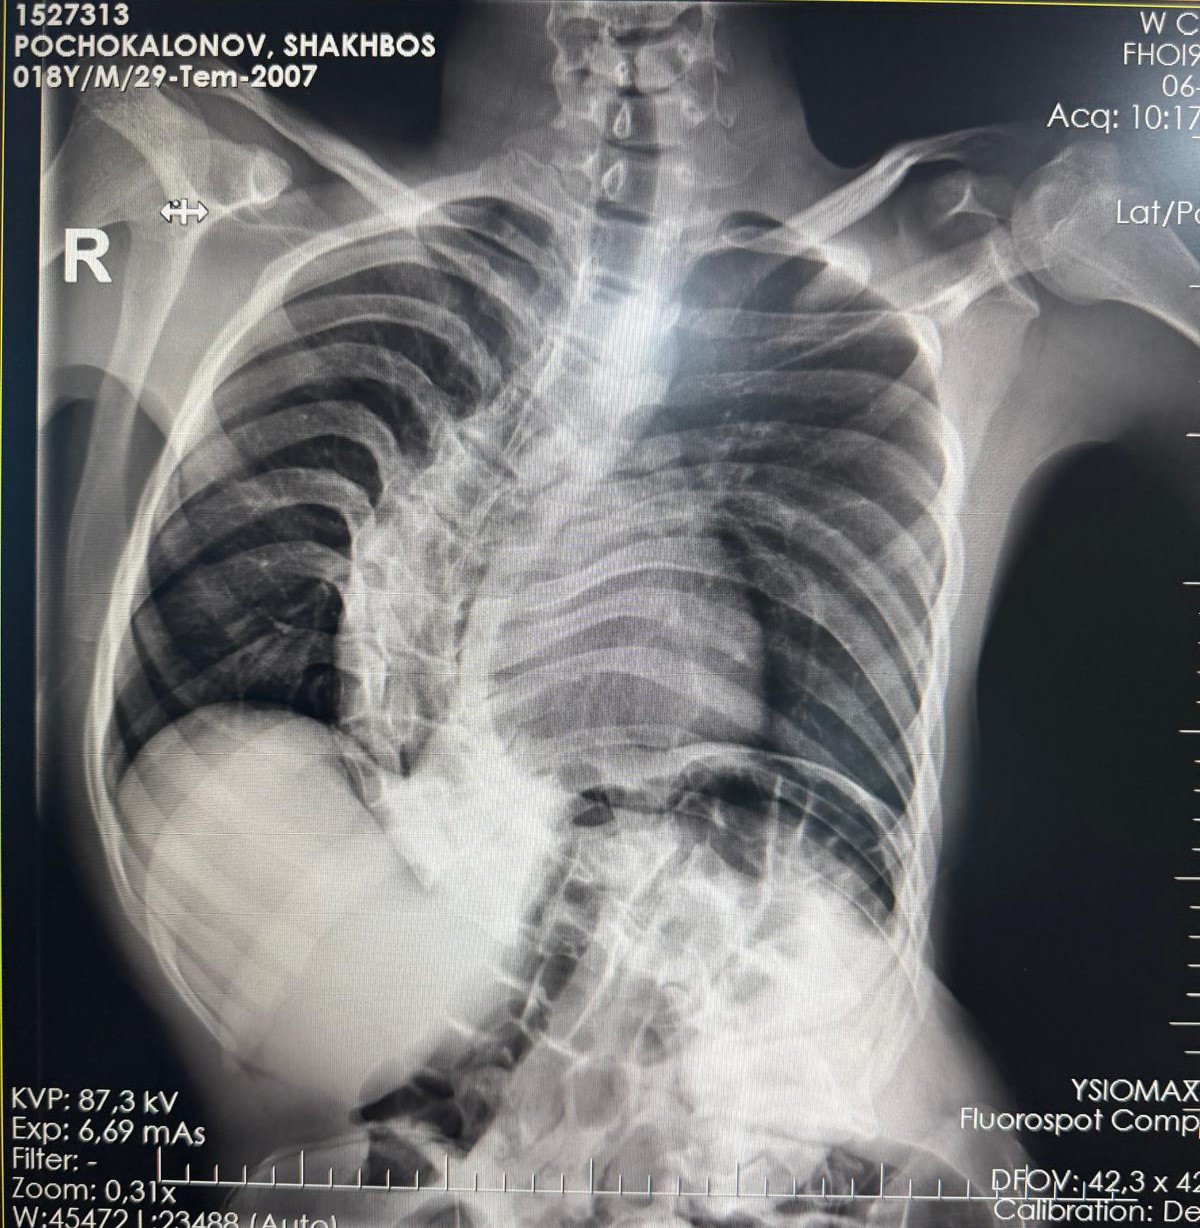

Başarılı geçen ameliyat sonrası hastanın yaşam kalitesinin önemli ölçüde arttığını belirten Ortopedi ve Travmatoloji uzmanı Prof. Dr. Mehmet Atıf Erol Aksekili, skolyoz hakkında bilgi vererek, "Skolyoz kısaca omurganın S şeklini almasıdır. Ön-arka planda omurganın S şeklini almasını biz kısaca skolyoz diyoruz. Skolyoz en sık adolesan dediğimiz ergenlik döneminde görülür. Ancak diğer hastalıklarla birlikte görüldüğünde daha ileri seviyelerde karşımıza çıkabilir. Hastamız 18 yaşında bize başvurdu. Nöromüsküler skolyoz dediğimiz, nörolojik hastalıkların eşlik ettiği bir skolyoz tipi mevcut. Bu skolyozlar erken yaşta ortaya çıkar ve daha hızlı ilerler. Bu yüzden hastamız bize 90 dereceden daha ileri bir seviyede başvurdu" dedi.

Erken teşhis edilmesi halinde daha az cerrahi ile daha iyi sonuç alınabileceğini belirten Aksekili, "Skolyoz erken tanındığında fizik tedavi, egzersiz ve korseleme gibi yöntemlerle ilerlemesini kontrol altına alabiliyoruz. Hastamızda ileri skolyoz olduğu için iki aşamalı cerrahi uygulandı. İlk aşamada Halo Femoral traksiyon yöntemiyle skolyoz kısmen düzeltildi. İkinci aşamada ise vidalar, rodlar ve osteotomi ile omurga düzeltildi" diye konuştu.